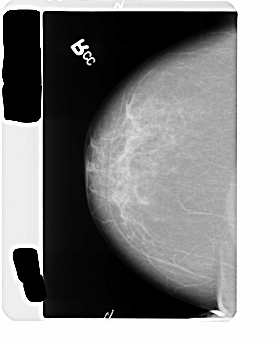

B_3476_1.LEFT_CC

LEFT_CC LINES 4504 PIXELS_PER_LINE 2912 BITS_PER_PIXEL 12 RESOLUTION 50 OVERLAY

FILE: B_3476_1.LEFT_CC.OVERLAY

TOTAL_ABNORMALITIES 1

ABNORMALITY 1

LESION_TYPE CALCIFICATION TYPE PLEOMORPHIC DISTRIBUTION CLUSTERED

ASSESSMENT 4

SUBTLETY 3

PATHOLOGY MALIGNANT

TOTAL_OUTLINES 1

BOUNDARY